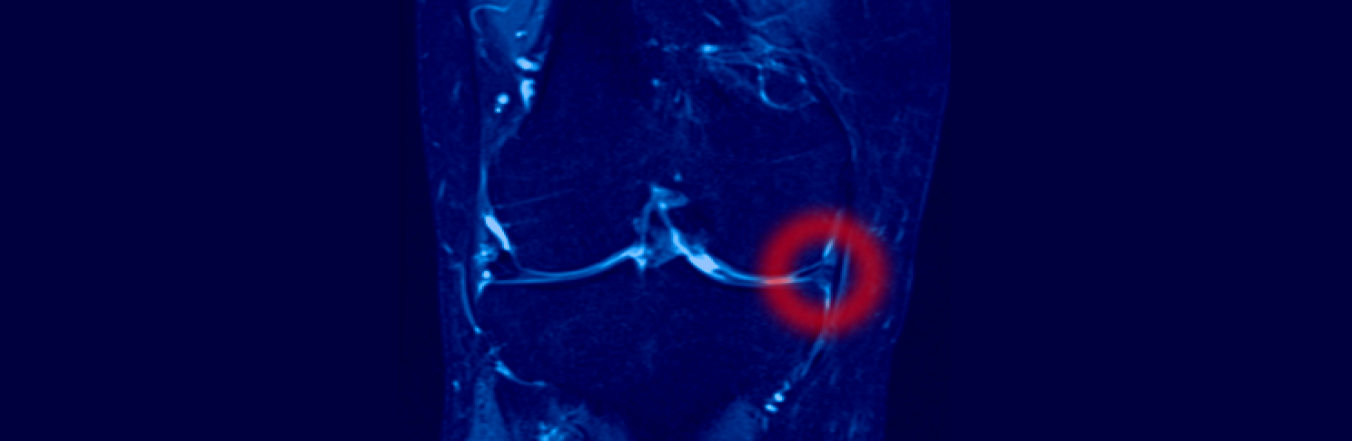

Risonanza magnetica

Per la diagnosi delle lesioni cartilaginee, si osservano segni come gonfiore, crepitii articolari e limitazione del movimento, ma è soprattutto la risonanza magnetica (RM) a svolgere un ruolo cruciale, offrendo immagini dettagliate dei tessuti molli dell’articolazione, tra cui menischi, cartilagine e legamenti.

RM ad alto campo

(almeno 1.5 tesla) è preferibile, perché garantisce maggiore sensibilità e precisione nel visualizzare anche piccole lesioni.